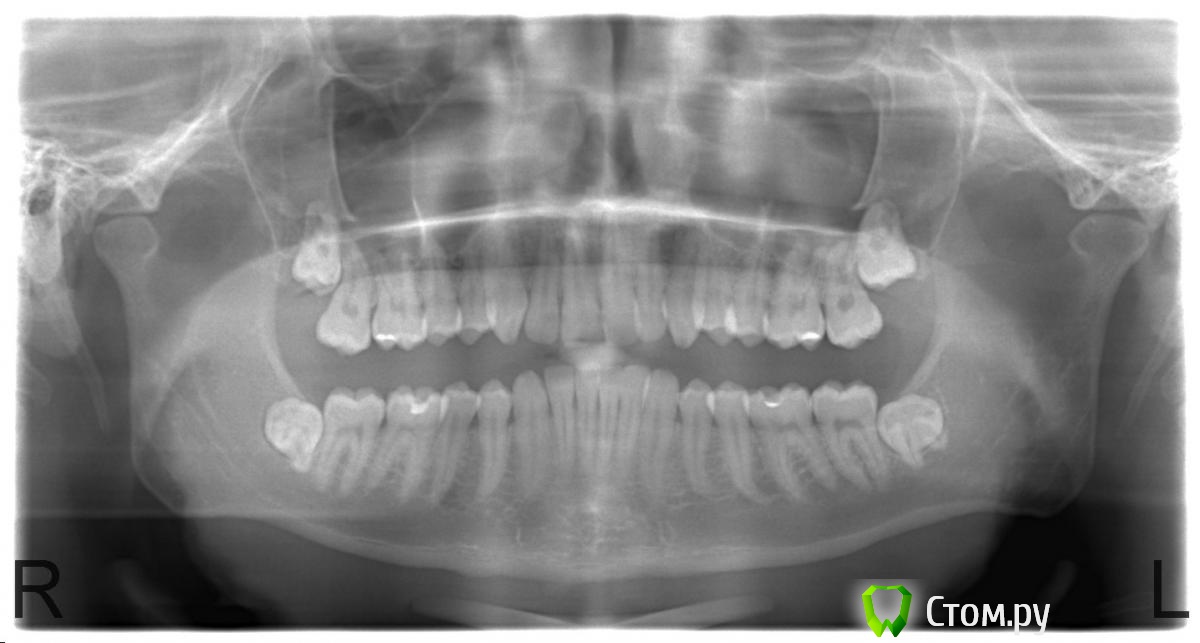

faity Опубликовано 30 июля, 2014 Поделиться Опубликовано 30 июля, 2014 (изменено) смотрим 4.8это после к сожалению в процессе удаления остались только мелкие фрагменты, не хотелось мягкие ткани сильно распахивать дистальный корень 90 градусов, медиальный 130-150 Изменено 30 июля, 2014 пользователем faity 4 Ссылка на комментарий